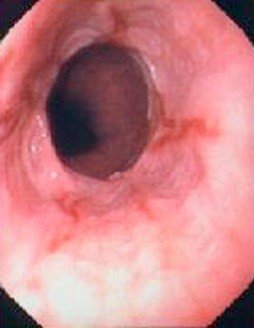

Diaqnozun dəiqiləşdirilməsi üçün kontrastlı Rentgenoloji müayinələr, KT və çox ehtiyatla endoskopiya edilir.

- Endoskopiya - divertikulun perforasiyası təhlükəsinə görə çox ehtiyatla aparılmalıdır.

Xəstəliyin dəqiqləşdirilməsi üçün kontrastlı Rentgenoloji müayinə, KT və çox ehtiyatla endskopiya edilməlidir.

Diaqnozun dəqiqləşdirilməsi üçün kontrastlı şüa diaqnostikası üsulları (Rh-qrafiya və ya KT) və endoskopiya aparılmalıdır.

- Endoskopiya - divertikulun perforasiyası təhlükəsinə görə çox ehtiyatla aparılmalıdır. QB-nun xəstəliklərinin və paraezofageal yırtıqların diferensiasiyası üçün mühümdür.